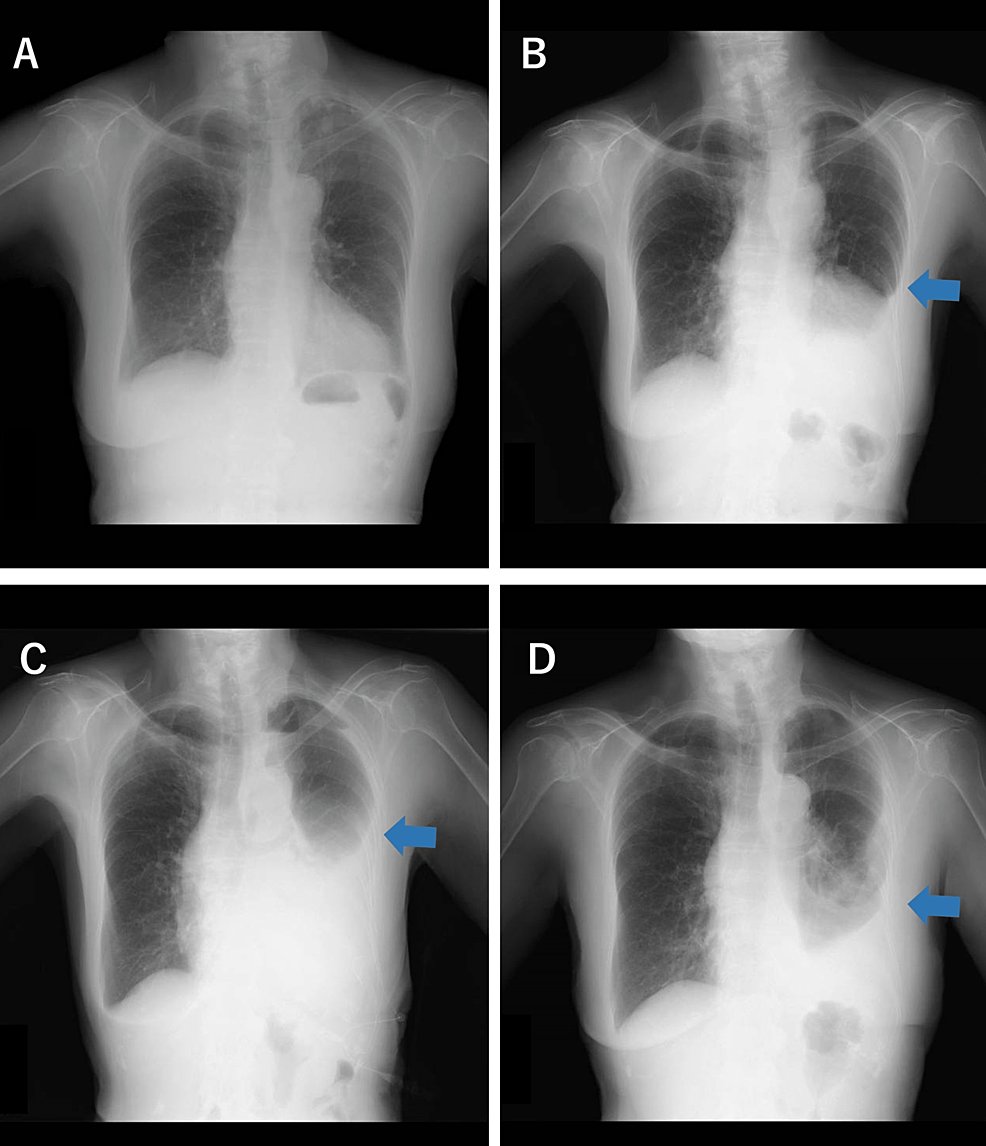

From www.cureus.com

Cureus Intractable Pleural Effusion After Stereotactic Ablative Does Chronic Bronchitis Show Up On A Chest X Ray Chronic bronchitis most often results from overproduction and hypersecretion of mucus by goblet cells. Imaging can show your provider if there’s any. Blood tests may be used to check for signs of. In some cases, recurrent bronchitis can lead to chronic respiratory issues. Bronchitis does not generally require further investigation. (if you have shortness of breath, chronic bronchitis may limit. Does Chronic Bronchitis Show Up On A Chest X Ray.

Physiotherapy Approach for Treating Bronchopneumonia A Case Report Does Chronic Bronchitis Show Up On A Chest X Ray Bronchitis does not generally require further investigation. Imaging can show your provider if there’s any. Spirometry is a common lung function test your provider may use if they think you have chronic bronchitis. Chronic bronchitis most often results from overproduction and hypersecretion of mucus by goblet cells. In some cases, recurrent bronchitis can lead to chronic respiratory issues. (if you. Does Chronic Bronchitis Show Up On A Chest X Ray.